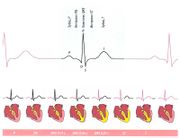

| 03:19, 20 июля 2016 | Mishci sport72.jpg (файл) |  |

34 КБ | Anes | Электрокардиограмма сердца | 1 |